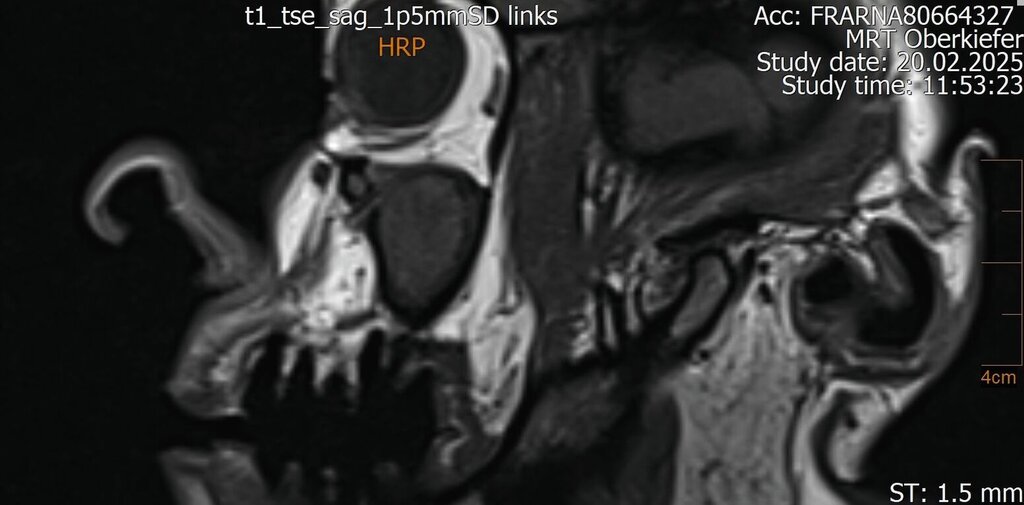

Im Februar 2022 stellte sich die 46-jährige Patientin nach Überweisung durch die Hauszahnärztin mit seit zwei Wochen bestehenden Schmerzen im linken Oberkiefer in einer MKG-chirurgischen Praxis vor. Klinisch und radiologisch zeigten sich eine tiefe Karies an Zahn 26 mit apikaler Ostitis und enger Beziehung zur Kieferhöhle (Abbildung 1) sowie der devitale Zahn 27.

Der Wendepunkt erfolgte schließlich im Februar 2025 im Rahmen einer Kontrolluntersuchung bei der Hauszahnärztin. Diese nahm die langjährige Beschwerdesymptomatik ernst und veranlasste eine MRT-Untersuchung am Deutschen Zentrum für Dentaldiagnostik (DZD). Die MRT-Bildgebung ergab eine chronische Osteomyelitis im Bereich der Extraktionsregion von Zahn 27 sowie eine ausgeprägte apikale Ostitis an Zahn 26 mit vollständiger Verschattung der linken Kieferhöhle und Ausdehnung der Entzündung ins Siebbein und in die Stirnhöhle. Auch konnte durch den befundenden Radiologen eine interradikuläre Fistelung an Zahn 26 erkannt werden, weshalb die Sinusitis als odontogen eingestuft wurde (Abbildungen 4 bis 7).